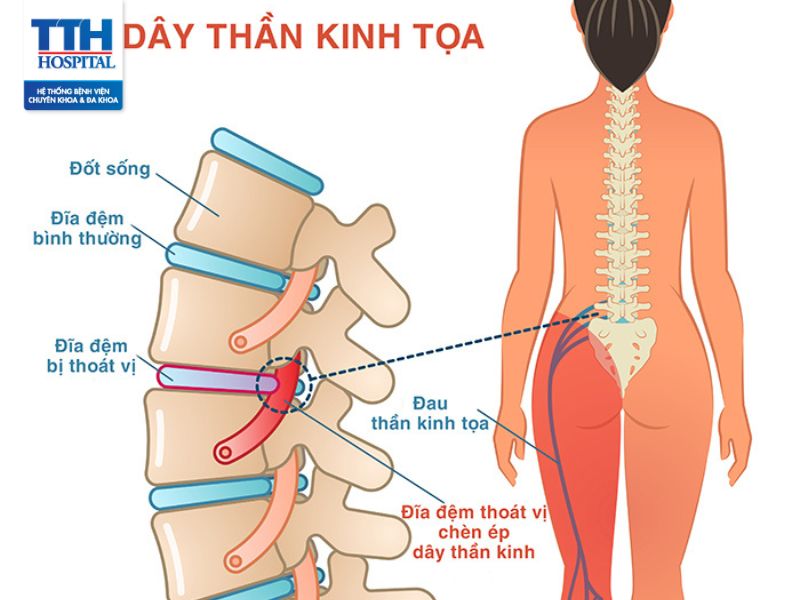

Đau dây thần kinh tọa thường xuất hiện khi có vấn đề về đĩa đệm đệm, sự trượt của đĩa đệm, sưng viêm cơ bắp, xương gai, hoặc áp lực lên thần kinh tọa do các vấn đề về cột sống.